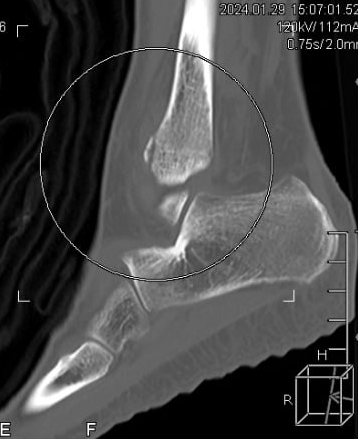

CT상 발목 골절로 진단

CT검사상

사고 초기 찍었던

엑스레이에서

미처 발견하지 못했던

발목 골절이

진단되었습니다.